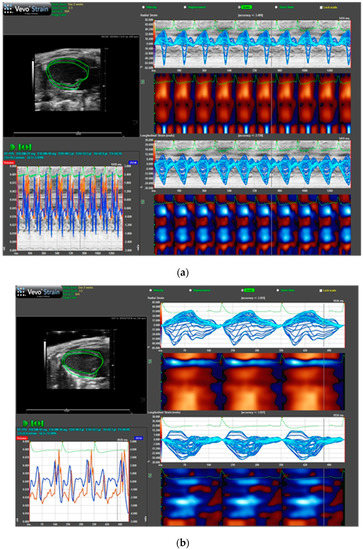

2.5. Biopolymer-Delivered Dox Does Not Affect Cardiac Function as Free Dox